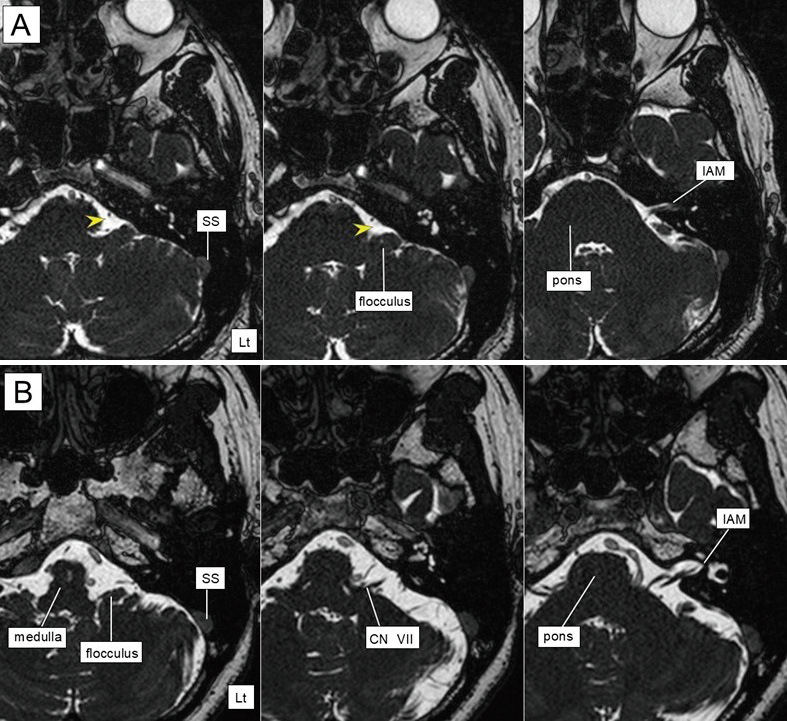

全内窥镜微血管减压术越来越多地被用于治疗面肌痉挛;然而,其疗效必须通过与常规显微微血管减压术的比较来验证。在本研究中,我们旨在比较显微手术和内窥镜下微血管减压治疗面肌痉挛的手术效果,并讨论内窥镜治疗的有效性和风险。回顾性分析2016 - 2022年在同一医院收治的40例面肌痉挛患者,其中显微微血管减压组33例(微血管减压组),全内镜微血管减压组7例(选择桥小脑池有足够空间进行内镜操作的患者)。对微血管减压组和内镜下微血管减压组进行统计分析,比较患者背景和手术结果。两组患者在年龄、性别、受累侧均无显著差异。在6个月的随访中,两组85%以上的患者均有明显改善。内窥镜微血管减压组比微血管减压组更常见延迟性面瘫和轻度下颅神经麻痹,如声音嘶哑等,但两组并发症发生率无显著差异。术后3个月内并发症均得到缓解。在内窥镜微血管减压过程中,由于小脑岩石表面的空间有限,内窥镜和器械之间的干扰可引起神经损伤。我们的研究结果表明,内窥镜手术不能总是用来代替传统的显微微血管减压。

Fully endoscopic microvascular decompression is increasingly being used to treat hemifacial spasm; however, its efficacy must be validated by comparing it with conventional microscopic microvascular decompression. In this study, we aimed to compare the surgical outcomes of microsurgical and endoscopic microvascular decompression for hemifacial spasm and discuss the usefulness and risks of endoscopic treatment. A total of 40 patients with hemifacial spasm were retrospectively evaluated at a single institution between 2016 and 2022, including 33 patients who underwent microscopic microvascular decompression (microvascular decompression group) and 7 patients who underwent fully endoscopic microvascular decompression group, which was chosen for patients with sufficient space in the cerebellopontine cistern for endoscopic manipulation. Statistical analyses of the microvascular decompression group and the endoscopic microvascular decompression group were performed to compare patient background and surgical outcomes. No significant differences in age, sex, or affected side were observed between the 2 groups. At the 6-month follow-up, substantial improvement was observed in more than 85% of the patients in each group. Delayed facial palsy and mild lower cranial nerve palsy, such as hoarseness, were more common in the endoscopic microvascular decompression group than in the microvascular decompression group, although there were no significant differences in the rate of complications between the 2 groups. All complications were alleviated within 3 months after surgery. During endoscopic microvascular decompression, interference between the endoscope and instruments can cause neural damage owing to the limited space along the petrosal surface of the cerebellum. Our results suggest that endoscopic procedures cannot always be used as a substitute for conventional microscopic microvascular decompression.